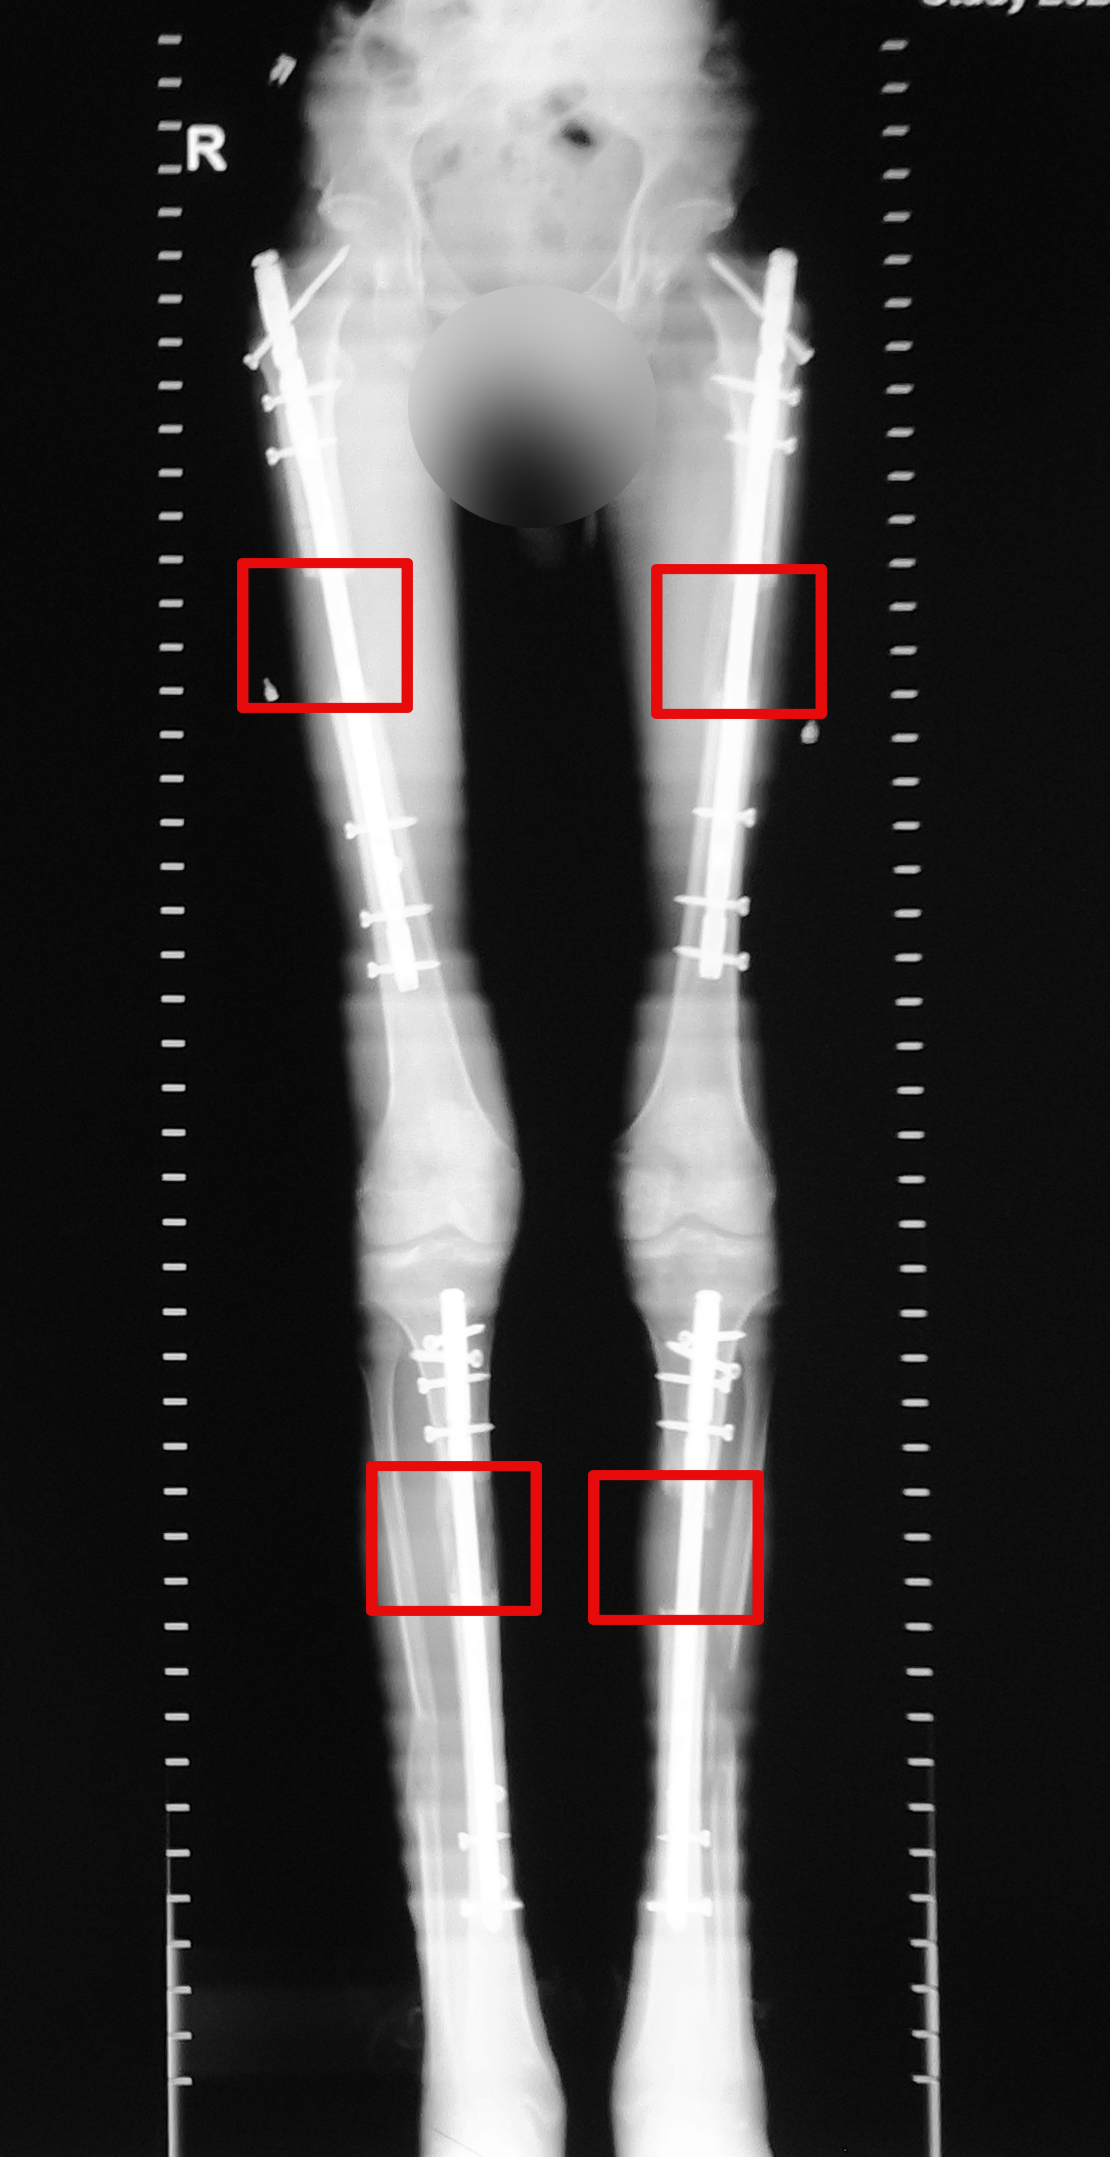

To be short, I underwent 3 surgeries and finished treatment with 4 implants in legs within 6 months. I attached 2 CT scans – before and after with 4 implants. I will lie if I say the treatment was an easy procedure. There are days when the pain is stronger than average but I could manage it by taking painkillers, do physical exercises. By the way, I had a physical therapy 6 times a week․ I worked with the physical therapist for one hour, but continued doing exercises, walking a few times a day. Honestly, it was hard but I realized the difficulties and more important, it was my decision to become taller.

Last year, I visited Armenia for a short period to remove my implants. Now I can say, that I have no problem, I can run, I go to gym almost every day. I am still in contact with my limb lengthening friends. They all are good. We even forget that we lengthened our legs.